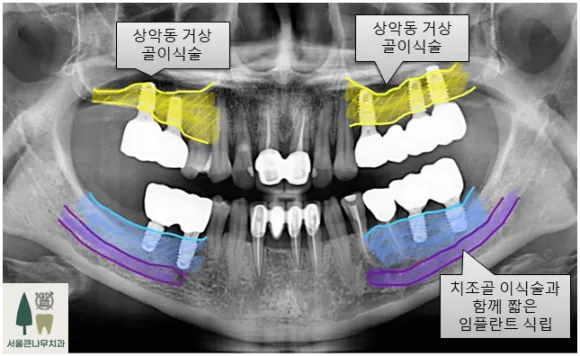

치료후 파노라마 엑스레이 사진

위턱 임플란트의 경우, 1-2mm 밖에 없을 정도로 매우 얇았던 상악 치조골이 상악동 거상을 이용한 골이식을 통해 치조골량이 많아진 모습이 보이시나요?

아래턱 임플란트의 경우, 잇몸뼈가 많이 주저앉아 신경관(보라색선)과 매우 가까워져 있었으나, 하악골 치조골 이식술을 통해 잇몸뼈를 만들어주고 짧은 임플란트를 식립하여 양쪽 모두 골고루 잘 씹을 수 있게 해드렸습니다.